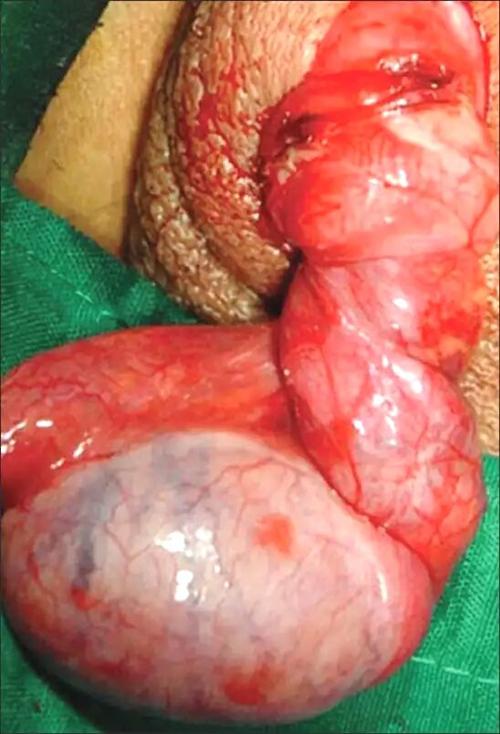

睾丸扭转手术示例 |

睾丸扭转病例图片 |